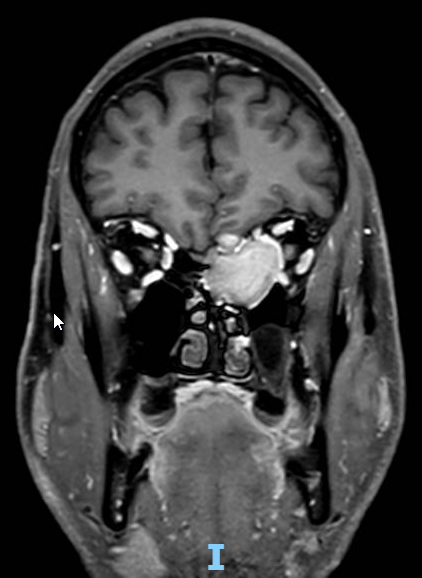

The patient (male, 55yo) presented with sudden visual loss in the right eye and was found to have a mass in the left ethmoidal sinus.

MRI brain showed the ethmoidal lesion was likely benign (e.g. fibrous dysplasia or ossifying fibroma), though a low-grade tumor could not be excluded. Biopsy was recommended.

3. Compression by ethmoidal lesion

• Unlikely: lesion is on the left, neuropathy is on the right

• No compressive signs on MRI

I believe tumoral compression is adding to NAION here to make the vision worse

There is no way thar ethmoid mass is knot compressing the optic nerve and exacerbating the underlying NAION.  Also it would allow you the rule out A massive Aspergilloma but if it were a fungus patient would be dead by now

I missed this originally also, Scott. While impressive, It's on the wrong side (I'm surprised that optic nerve ipsilateral to the tumor is unscathed!).

Posted 07-28-2025 14:58

I am sorry but the image orientation indicates a right ethmoidal mass , but the text say left .. then it wouldn't be compressing if this is the case

In a case like this, I would try to be sure the scan is oriented and labelled correctly. I have seen several cases where the radiology indicated the wrong side (yes - in MRI and CT). A head CT might help elucidate the  type of lesion  you're dealing with as well as verify the side is correctly identified.

I would definitely say that compression played a role from the images , I may be a contributing factor , I had a sphenoidal wing meningioma with an attitudinal defect , it is a large mass to be omitted as a factor